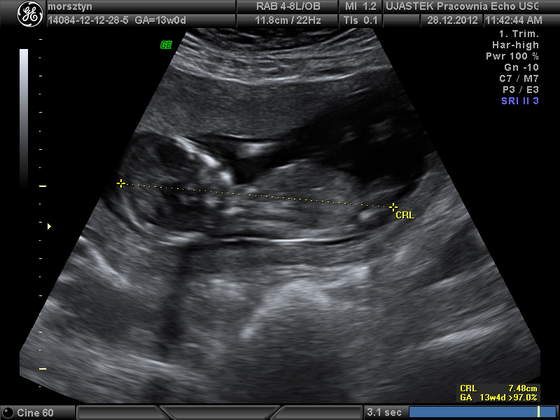

Joanno, gratuluję udanej wizyty, piękne zdjęcie, super, ze coreczka sie ujawnila